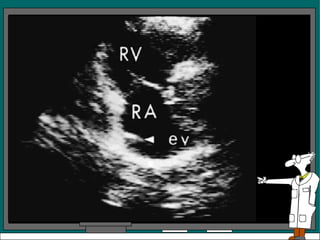

Variantes normales:

• Valvula de Eustaquio prominente en la AD en su

union con la vena cava inferior se ve en

paraesternal eje largo y en vista de 4 cámaras